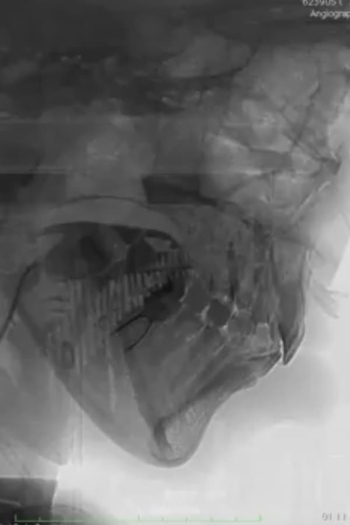

In which the artist shows a 3D scan of her lower lip, confronting her fragile health.